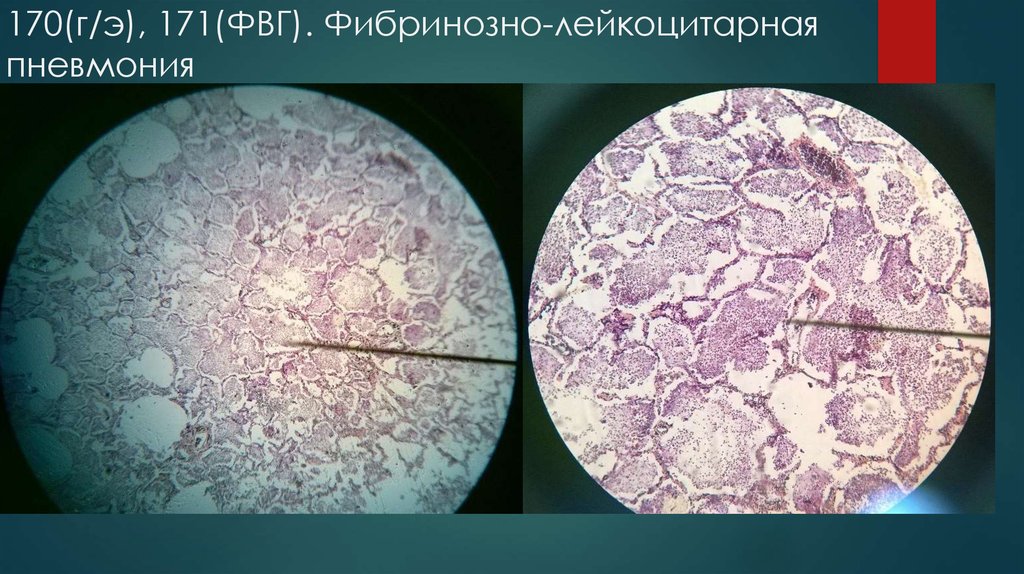

Карнификация Легкого: Микропрепараты и Диагностика

Раздел: Калейдоскоп образов